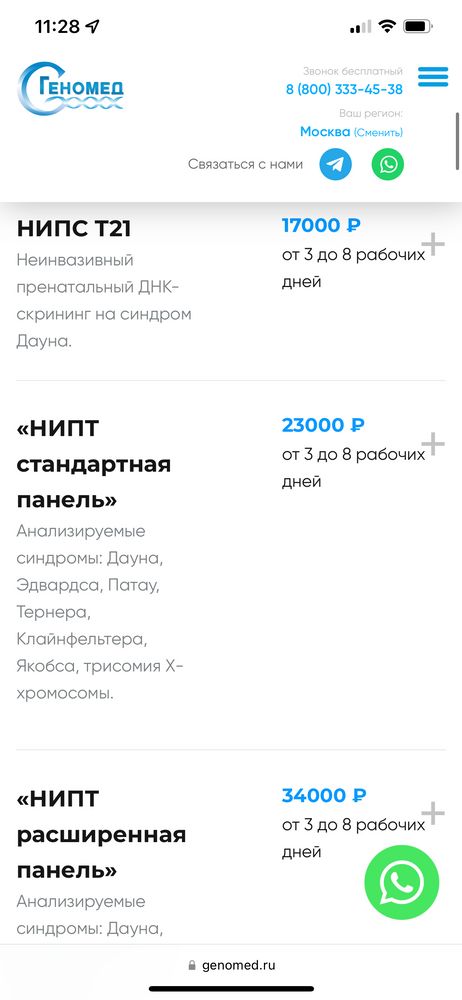

Что по срокам? Сдавала я расширенную панель в России. 14.08 я сдала кровь, 16.08 она поступила в лабораторию 21.08 в вс вечером пришел результат.

По результатам все хорошо! Малыш здоров, со спокойной душой пойду 29.08 на скрининг. Инициатива сдать такой тест полностью с мужем наша. Я вообще считаю что этот тест как в Америке должен быть у нас полностью бесплатным, а ещё лучше обязательным. Потому что статистика показывает, что 20% результатов скрининга ложно-отрицательные. Даже тот лучший врач города, которого я выбрала для скрининга допускал ошибки.